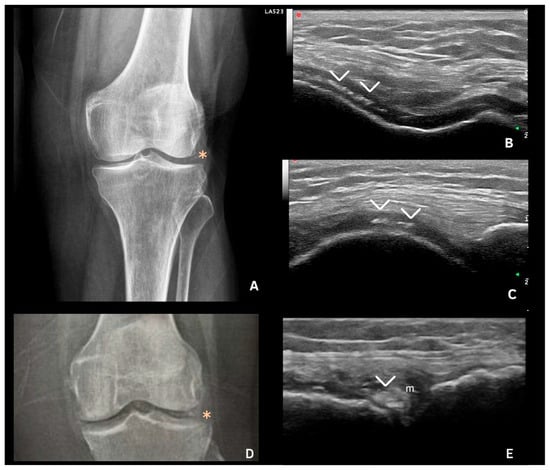

- Filippou, G.; Frediani, B.; Gallo, A.; Menza, L.; Falsetti, P.; Baldi, F.; Acciai, C.; Lorenzini, S.; Galeazzi, M.; Marcolongo, R. A “new” technique for the diagnosis of chondrocalcinosis of the knee: Sensitivity and specificity of high-frequency ultrasonography. Ann. Rheum. Dis. 2007, 66, 1126–1128. [Google Scholar] [CrossRef] [PubMed]

- Filippucci, E.; Scirè, C.A.; Delle Sedie, A.; Iagnocco, A.; Riente, L.; Meenagh, G.; Gutierrez, M.; Bombardieri, S.; Valesini, G.; Montecucco, C. Ultrasound imaging for the rheumatologist. XXV. Sonographic assessment of the knee in patients with gout and calcium pyrophosphate deposition disease. Clin. Exp. Rheumatol. 2010, 28, 2–5. [Google Scholar] [PubMed]

- Gutierrez, M.; Di Geso, L.; Salaffi, F.; Carotti, M.; Girolimetti, R.; De Angelis, R.; Filippucci, E.; Grassi, W. Ultrasound Detection of Cartilage Calcification at Knee Level in Calcium Pyrophosphate Deposition Disease. Arthritis Care Res. (Hoboken) 2014, 66, 69–73. [Google Scholar] [CrossRef] [PubMed]

- Foldes, K. Knee chondrocalcinosis. Clin. Imaging 2002, 26, 194–196. [Google Scholar] [CrossRef]

- Lee, K.A.; Lee, S.H.; Kim, H.R. Diagnostic value of ultrasound in calcium pyrophosphate deposition disease of the knee joint. Osteoarthr. Cartil. 2019, 27, 781–787. [Google Scholar] [CrossRef]

- Filippou, G.; Scanu, A.; Adinolfi, A.; Toscano, C.; Gambera, D.; Largo, R.; Naredo, E.; Calvo, E.; Herrero-Beaumont, G.; Zufferey, P. Criterion validity of ultrasound in the identification of calcium pyrophosphate crystal deposits at the knee: An OMERACT ultrasound study. Ann. Rheum. Dis. 2021, 80, 261–267. [Google Scholar] [CrossRef] [PubMed]

| 1 | Hyperechoic bands, parallel to the surface of the hyaline cartilage |

| 2 | Thin hyperechoic spots in fibrocartilage |

| 3 | Homogeneous hyperechoic nodular or oval deposits in fibrocartilage |

| Fibrocartilage | Shape: Deposits of variable shape. Echogenicity: Hyperechoic (similar to the bone cortex echogenicity). Localization: Within the fibrocartilage structure. Dynamic scanning: Remain fixed and move together with the fibrocartilage during dynamic assessment. Examples: Menisci, TFC, hip labrum, and acromioclavicular joint. |

| Hyaline cartilage | Shape: Deposits of variable shape. Echogenicity: Hyperechoic, without posterior shadowing. Localization: Localized within the hyaline cartilage. Dynamic scanning: The deposits remain fixed and move together with the hyaline cartilage. Examples: Knee and MCP joint. |

| Pseudo-double contour sign | Shape: Deposits of variable shape. Echogenicity: Hyperechoic, without posterior shadowing. Localization: Localized at the chondro-synovial interface or in the joint capsule and adjacent ligaments. Dynamic scanning: Moves in the opposite direction of cartilage and adjacent bone. Examples: Knee, proximal, and distal radio-ulnar joint. |